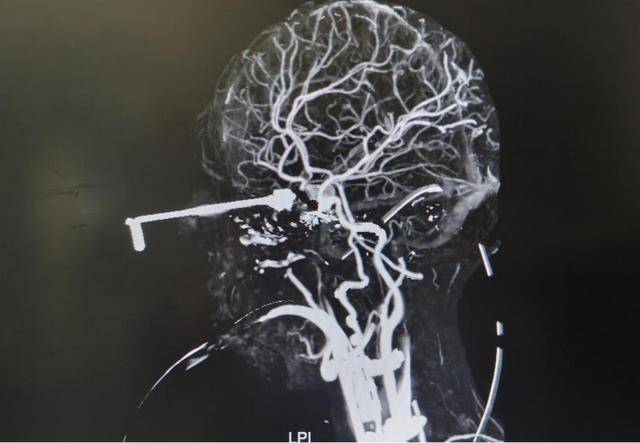

Theo thông tin từ bệnh viện, một bé trai 3 tuổi (tên đã được thay đổi) trong lúc chơi đùa đã vô tình cầm kim móc đan bằng kim loại – một vật dụng nhỏ, sắc và cứng. Khi người lớn không để ý, bé bị ngã, khiến đầu kim đâm xuyên từ vùng hốc mắt vào trong hộp sọ, gây tổn thương nghiêm trọng đến não bộ.

Ngay sau tai nạn, bé đau đớn khóc lớn, vùng quanh mắt sưng đỏ nhanh chóng. Đáng nói, loại kim móc này có cơ chế cánh mở, khi đâm vào sẽ mở ra, nhưng khi rút ngược ra, cánh khép lại, rất dễ móc vào mô mềm và mạch máu.

Do hoảng sợ và đau đớn, bé đã tự dùng tay rút chiếc kim ra khỏi đầu. Chính hành động này đã gây ra tổn thương thứ phát nghiêm trọng: mạch máu bị xé rách, xuất huyết não, dẫn đến nhồi máu não và biểu hiện yếu nửa người.

Bé nhanh chóng được đưa đến Bệnh viện Nhi Đại học Chiết Giang, nhập khoa cấp cứu trong tình trạng nguy kịch và được chuyển thẳng vào đơn vị hồi sức tích cực.

Các bác sĩ cho biết, ca phẫu thuật gắp dị vật vô cùng phức tạp vì kim đã dính chặt vào các mạch máu và dây thần kinh quan trọng. Ê-kíp phẫu thuật buộc phải thao tác cực kỳ cẩn trọng để tránh gây chảy máu ồ ạt hoặc tổn thương không hồi phục.

Rất may, sau nhiều giờ phẫu thuật, dị vật đã được lấy ra an toàn, không xảy ra biến chứng nghiêm trọng. Hiện tại, tình trạng của bé ổn định, thị lực được bảo toàn, các dấu hiệu yếu liệt do nhồi máu não đang dần cải thiện và bé đã bước vào giai đoạn phục hồi chức năng.